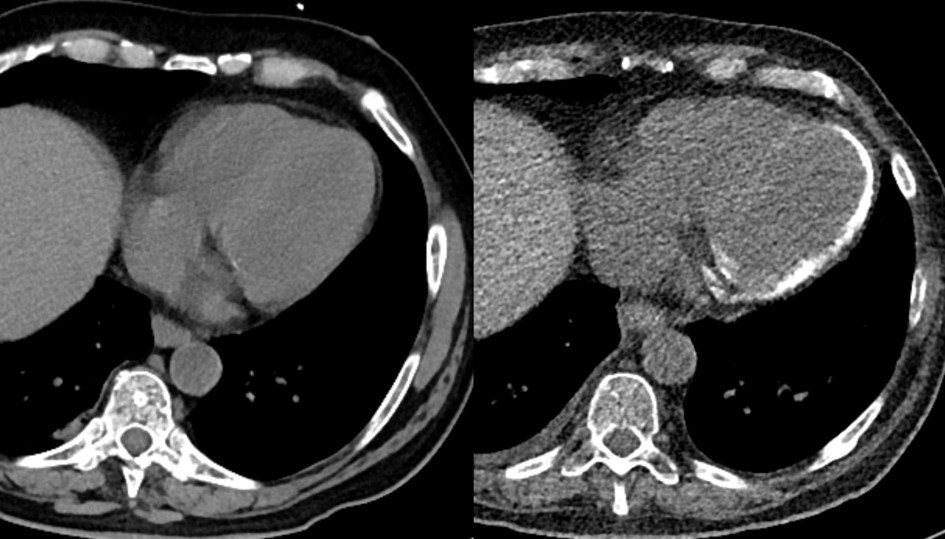

The reported case shall highlight severe sepsis as possible cause of myocardial calcification, as well as the highly dynamic development thereof within a time span of merely 10 weeks. A 60-year-old male patient had been admitted to hospital for palliative therapy of progressive multiple myeloma, which lately had transformed into plasma cell leukemia. After commencing his third therapy cycle with Elotuzumab, the patient suffered from a pneumogenic sepsis due to staphylococcus infection that required mechanical ventilation for 7 days. Antimicrobial therapy followed antimicrobial susceptibility testing and included Tazobactam, Piperacillin, and Fosfomycin. During his hospital stay, computed tomography images of the chest were acquired initially, i.e. at onset of pneumogenic sepsis (Figure 1.: left panel), as well as after 10 weeks (Figure 1: right panel) to follow-up pneumonia consolidations in both upper lung lobes. Surprisingly, non-contrast enhanced follow-up CT images revealed newly developed calcifications within the outer myocardial layers of the left ventricle.

Figure 1.Non-contrast enhanced CT scans of the chest initially during onset of pneumogenic sepsis (right) and after 10 weeks (left) show rapid development of non-preexisting, extensive myocardial calcifications.